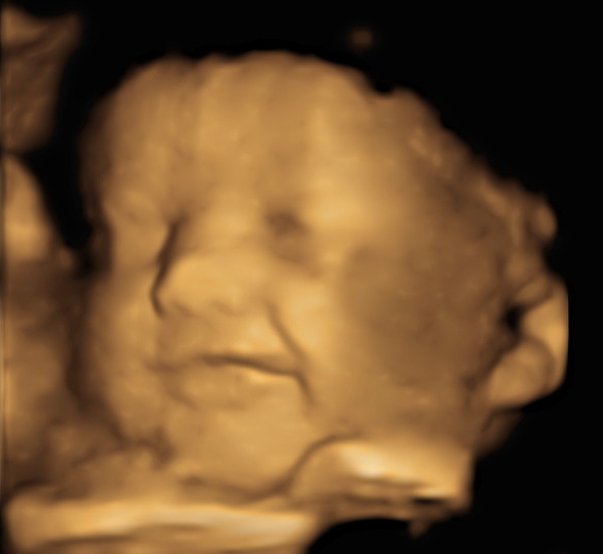

3D Imaging

Three-dimensional ultrasound images are a compilation of 2D images taken from multiple different angles to create your 3D image.

4D Imaging

Four dimensional ultrasound is basically the same as 3D images, except they show movement. With 4D imaging you can watch your baby move, suck their thumb, and yawn.

HD Imaging

HD imaging also known as 5D imaging, is the next level up from 4D. With more developed software, you can obtain images with much more detail allowing parents to see more characteristics of their baby!

3rd Trimester (28-40 weeks) - most clients tend to find that 30-34 weeks give the best 3D/4D/HD images. (See image calculator to determine best date range for your due date.)